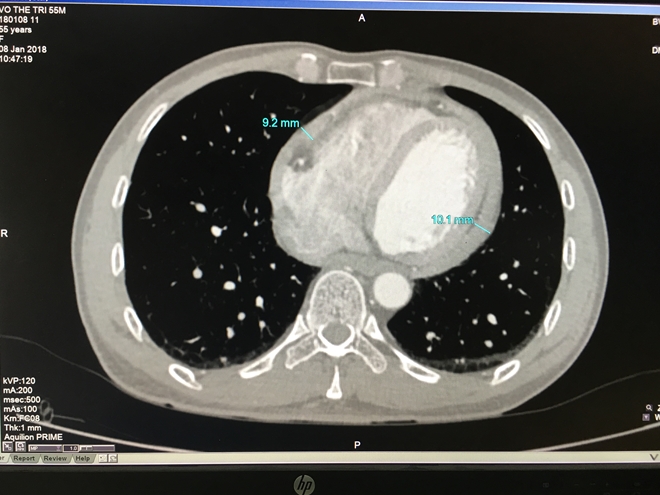

Màng tim xơ như 'mo cau' suýt lấy mạng người đàn ông

19:03 12/01/2018

Đó là trường hợp bệnh nhân V.T.T (55 tuổi, ngụ Hóc Môn, TP.HCM), được bệnh viện đa khoa Xuyên Á (BVXA) thông tin vào ngày 11-1-2018. Bệnh nhân đã được điều trị thành công dù ca phẫu thuật rất khó khăn.